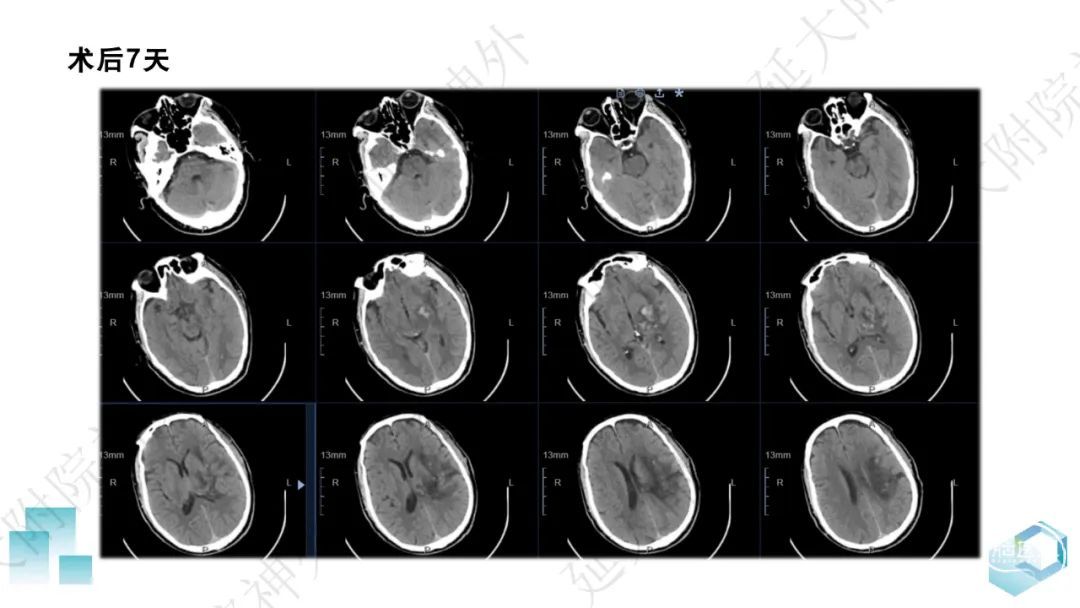

今天为大家分享的是《监测有道丨颅脑创伤-神经重症周刊》第332期,由延安大学附属医院神经外科贾云峰主任医师带来的:左侧基底节区出血破入脑室一例神经内镜下血肿清除术,欢迎阅读、分享。

长期从事神经外科疾病的基础与临床研究。专长于神经急危重症综合治疗、神经内镜脑出血微创手术、脊髓脊柱疾病显微外科微创治疗、颅内及脊髓肿瘤、脑血管病、脑、脊髓先天畸形的微创治疗。参与主持完成科研项目《尼莫地平对脊髓损伤的作用研究》等,获陕西省自然科学优秀论文奖。参与国家卫健委牵头的《自发性脑出血的多中心登记研究》等项目研究及《脑出血患者颅内压监测》《脑出血后脑水肿的治疗》专家共识的制定。以第一作者在国内外发表核心期刊20余篇,SCI收录文章1篇,多次应邀在中华医学会、中国医师协会全国神经外科学年会交流发言。主编及参编著作3部,国家发明专利2项